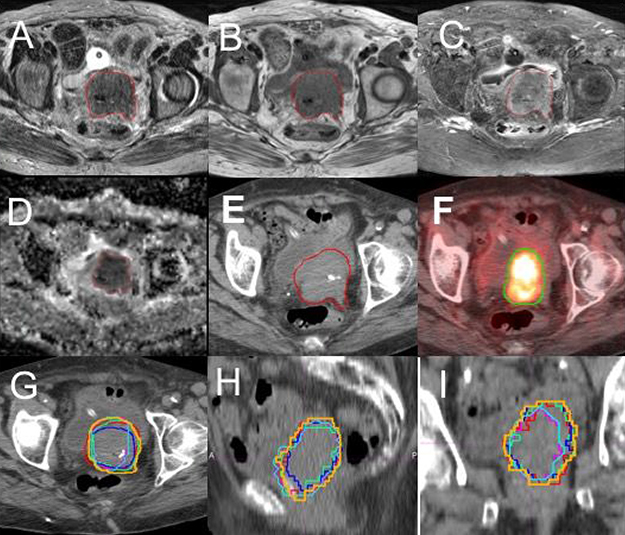

Differences between the GTVs delineated from the 4 MRI sequences, CT and PET were generally observed. Figure 1 presents GTV contours on the four MRI sequences, CT and PET on a same/similar axial slice for a representative case. It is clear that the GTVs from different imaging modalities or different MRI sequences are quite different. More quantitative data are described below.

Figure 1: Contours of gross tumor volume (GTV) on multiple imaging modalities for a representative patient. (A) T2-weighted MRI; (B) T1-weighted MRI; (C) T1 MRI with fat suppression and contrast (T1F+); (D) apparent diffusion-coefficient (ADC) maps; (E) CT; (F) FDG-PET with SUV = 2.5 threshold. The overlay of the six GTV contours, GTV-T1 (green), GTV-T2 (blue), GTV-T1F+ (red), GTV-ADC (light blue), GTV-SUV2.5 (pink) and GTV-CT (brown), on an axial (G), a coronal (H) and a sagittal (I) CT slices are shown.